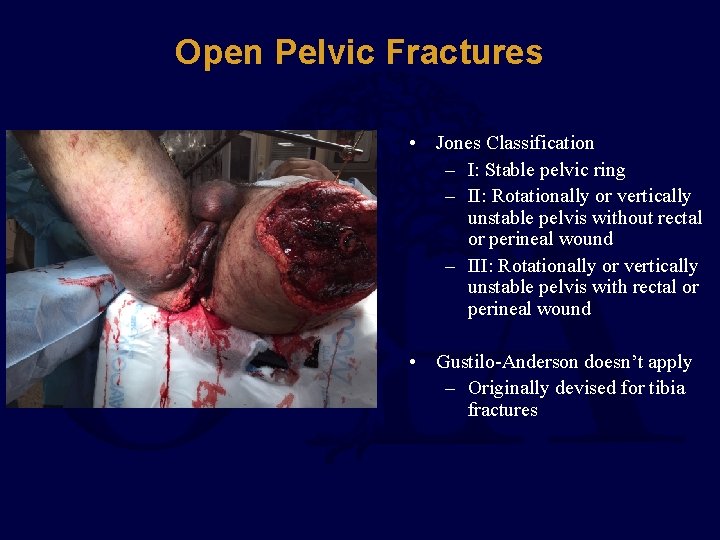

Open Pelvic Fractures • Jones Classification – I: Stable pelvic ring – II: Rotationally or vertically unstable pelvis without rectal or perineal wound – III: Rotationally or vertically unstable pelvis with rectal or perineal wound • Gustilo-Anderson doesn’t apply – Originally devised for tibia fractures